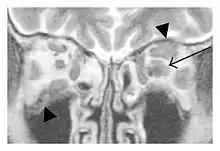

The extent of inflammation that can occur in IgG4-ROD is well demonstrated on magnetic resonance imaging (MRI).

Infraorbital nerve enlargement (IONE) is considered to be a particularly suspicious sign of IgG4-ROD, but seems to occur only when inflammation is in direct contact with the infraorbital canal.[10] IONE is defined as the infraorbital nerve diameter being greater than the optic nerve diameter in the coronal plane.

![]() Swelling of the left superior and lateral rectus muscles, a mass lesion around the left optic disc (arrow), and enlargements of the left supraorbital nerve and the right infraorbital nerve (arrow heads) in a 60-year-old man with a serum IgG4 of 463 mg/dL.[1] (T1-weighted MRI) |